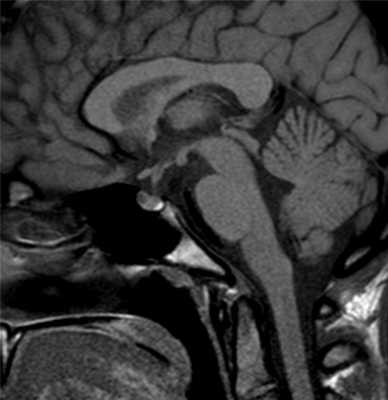

Гипофиз на снимке МРТ

МРТ гипофиза в норме